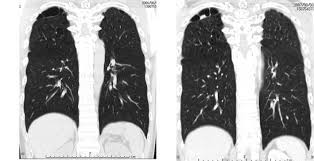

Most lung cancers don't cause symptoms until the disease has advanced, in part because the lungs have few nerve endings. Ct scan showing a cancerous tumor in the left lung. The scan only takes a few minutes and is not painful. Undergoing regular screening may be a good idea for people with a high risk of developing lung cancer. Lung cancer is the leading cause of cancer deaths in males and females in the united states.

Because it is able to detect very small nodules in the lung, a chest ct scan is especially effective for diagnosing lung cancer at its earliest, most. This method of ct scanning builds a detailed image of the body's internal workings. Early detection of lung cancer is being made easier through the use of ct scans. Lung cancer is the leading cause of cancer deaths in males and females in the united states. Around 44,500 people are there are usually no signs or symptoms in the early stages of lung cancer, but many people with if the ct scan shows there might be cancer in the central part of your chest, you'll have a bronchoscopy. This may reveal an obvious mass, the widening of. Most lung cancers don't cause symptoms until the disease has advanced, in part because the lungs have few nerve endings. The scan is painless and takes about 10 to 30 minutes. Ct scan showing a cancerous tumor in the left lung. Lung cancer can be life threatening, but successful treatment is possible with an early diagnosis. Ct scans to find lung cancer in smokers. It is used to look for early signs of lung cancer. Radiological scan is useful in detecting early npc.